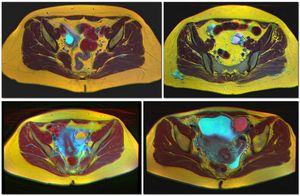

질식 초음파 검사로 촬영한 67 x 40 mm 크기의 자궁내막종으로, 다소 과립상의 내용물을 보입니다. - 난소에 생긴 자궁내막증으로 인한 것이다.